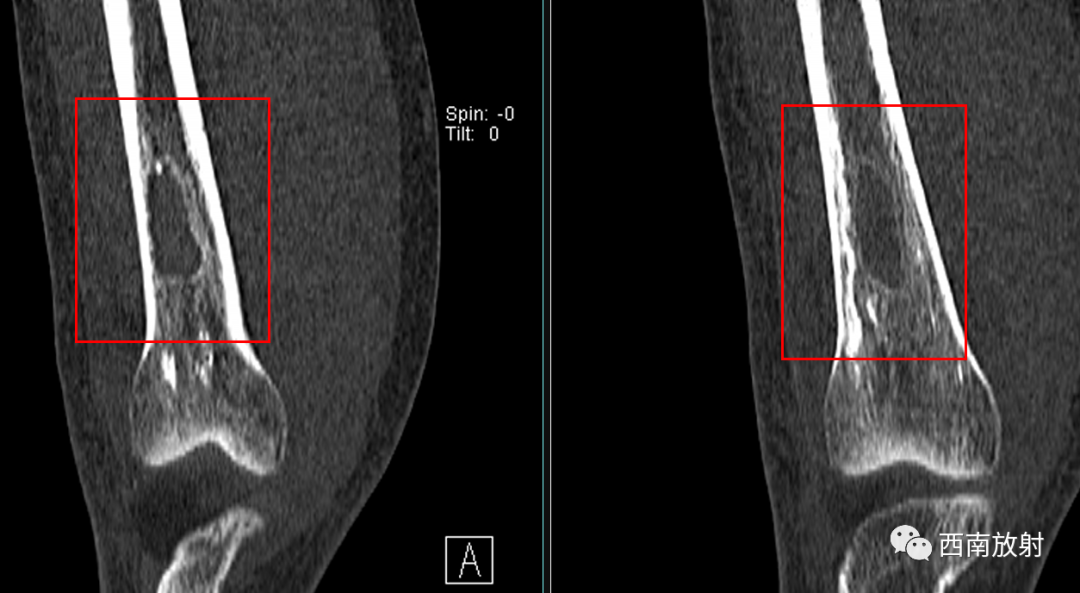

大体病理:右大腿中下段内侧骨膜外见一腔隙,约3X3X4cm,内有较多血凝块,有少许脓液,股骨下段周围有少许脓液,少量疤痕形成,右膝关节内有少许脓液,见有少许脓苔,右骨髓腔未见破坏,骨髓腔内有少许脓液,已被疤痕织包裹。

诊断:慢性骨髓炎,周围软组织脓肿。

CT显示骨破坏、脓肿、死骨及骨膜增生、骨质增生硬化,呈骨小梁密度增高、模糊,髓腔密度增大、狭窄,皮质增厚。MRI显示早期骨髓内广泛分布的斑片异常信号,与邻近正常骨髓信号相比较,T1WI信号减低,T2WI信号增高,脂肪抑制T2WI 或STIR 等序列上病变显示更清楚,骨皮质周围软组织内呈弥漫分布的T1WI低信号及T2WI高信号影,边界模糊。出现骨膜反应,骨皮质不规则破坏,脓肿及死骨形成。

▲骨破坏区及硬化边

▲广泛骨膜增生